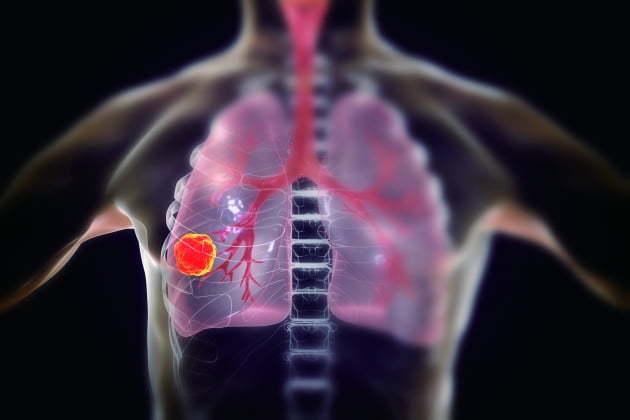

폐암의 초기증상 중에 흉통이 있습니다. 폐암 환자의 약 1/3이 흉통을 호소합니다. 흉통의 원인은 폐 가장자리에 종양이 형성되어 암세포를 생성하고 흉벽과 흉막에 침착되어 통증을 유발하는 것입니다.

흉통의 원인은 여러 가지가 있을 수 있지만, 오늘날 우리가 다루고 있는 폐암으로 인한 흉통은 경미한 통증보다는 지속적인 따끔거림과 둔한 통증을 동반한다는 점에 유의하시기 바랍니다. 또한 암은 흉막이나 흉벽 대신 갈비뼈로 퍼져 통증을 유발할 수 있습니다. 종양은 주변 조직 세포를 자극할 수 있으므로 계속해서 통증을 유발하는 경우 의사의 진찰을 받는 것이 좋습니다.